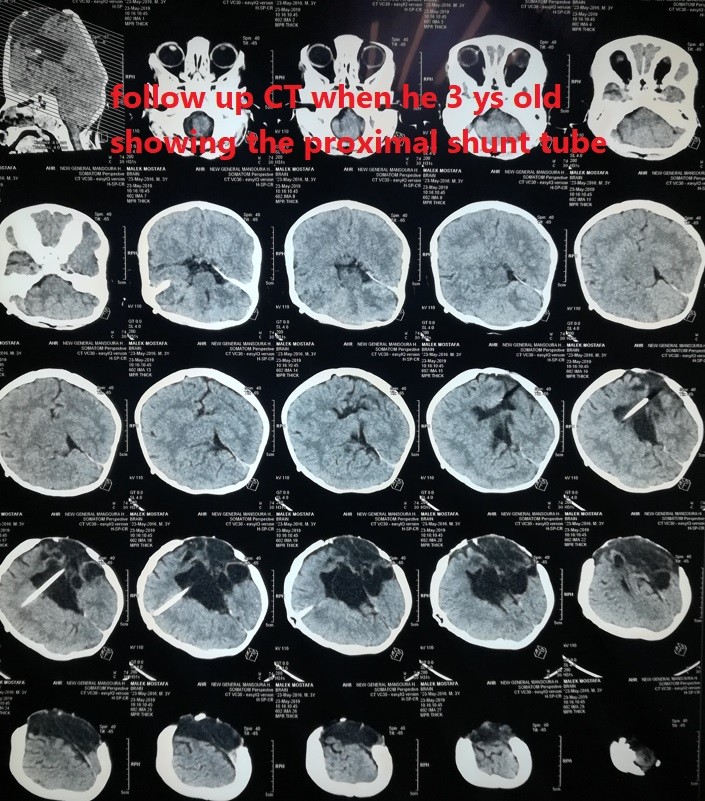

صور لحالة كاملة تم متابعتها منذ الأسبوع الأول من الولادة وحتي عمر ثلاث سنوات لطفل يعاني من قيلة مخية سحائية كبيرة .